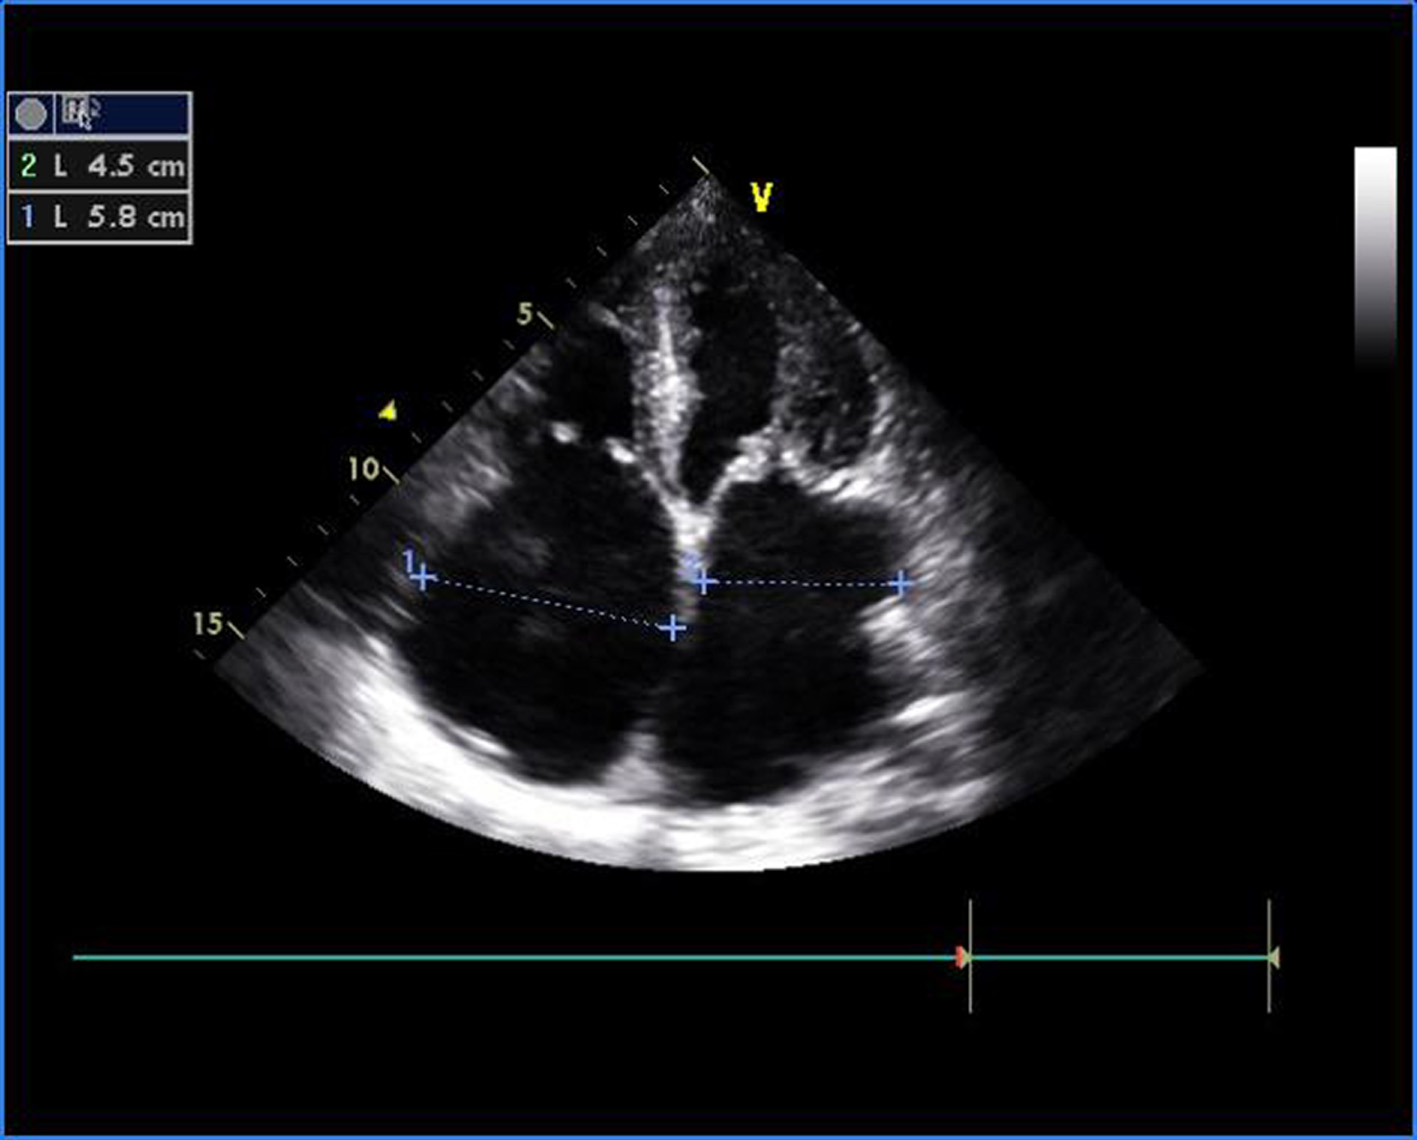

Figure 1. Transthoracic echocardiogram of apical four-chamber view showing thickened and doming mitral valve and tricuspid valve.